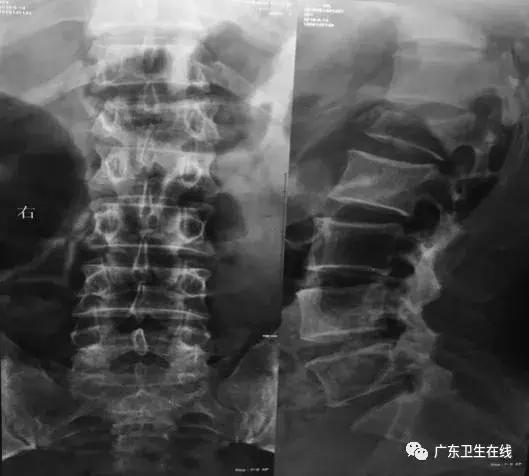

通过磁共振检查,专家团队还发现,患者第一次手术做得并不彻底,钉子所打的位置不对 ,导致术后症状没有改善,反而对腰椎形成了新的压迫。

术中可见,患者胸左侧椎弓根的螺钉穿入了椎管,压迫脊髓;腰1、腰2椎体严重压迫脊髓。这与术前判断吻合,患者受伤程度比预计还要严重。